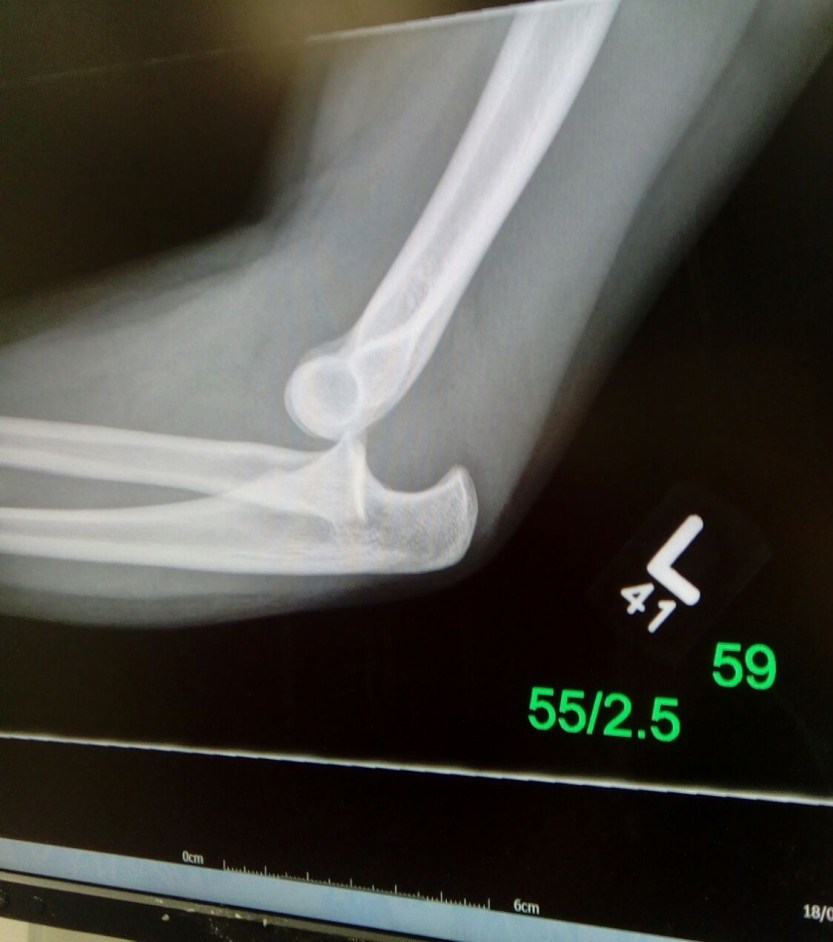

In fact I saw this one yesterday in a 13 year old girl. It has been reduced and was recovering well but, well, it should have been avoided. How? Teach falling practice falling.